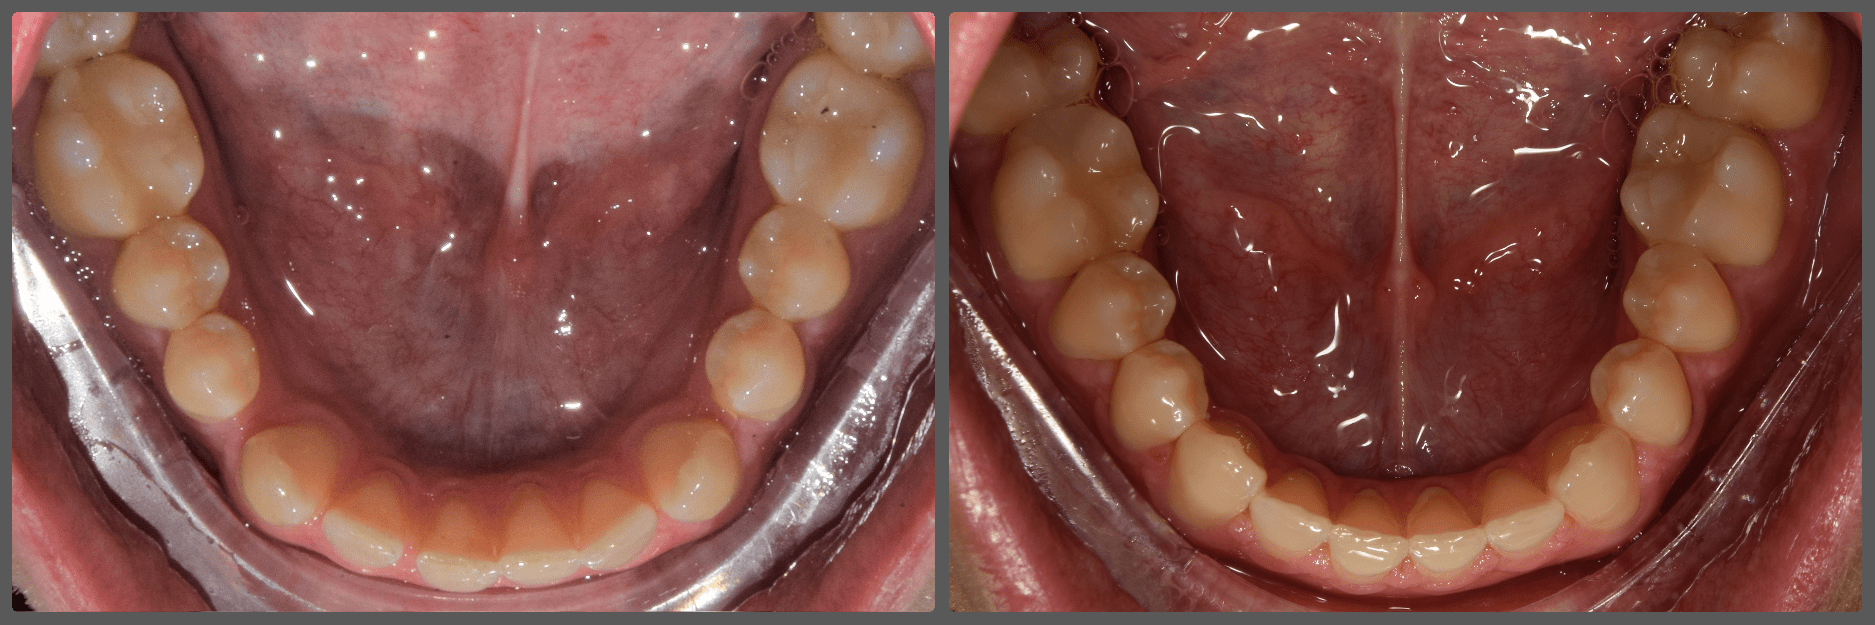

Bálint a 90 fokban elfordult jobb felső kismetszője miatt keresett meg engem. A vizsgálatokat követően kiderült, hogy a probléma ennél jóval komplexebb: súlyos keresztharapást, súlyos mélyharapást és felső rágósík billenést diagnosztizáltam nála. Alsó-felső H4 önligírozó fogszabályozó készülék, intermaxilláris gumihúzás és elülső harapásemelők segítségével korrigáltuk az eltéréseket. A bal oldali rágósík billenést fogszabályzási miniimplantátum alkalmazásával oldottuk meg. A bal felső-elülső fogakat felfelé mozgattuk, a miniimplantátumhoz húzva. Bálint esete igen komplex volt, ám kiváló együttműködésének köszönhetően 26 hónap alatt végeztünk a kezelésével (beleértve a 2-3 hónapos COVID-19 miatti leállást is). Az eredmény úgy gondolom magáért beszél!